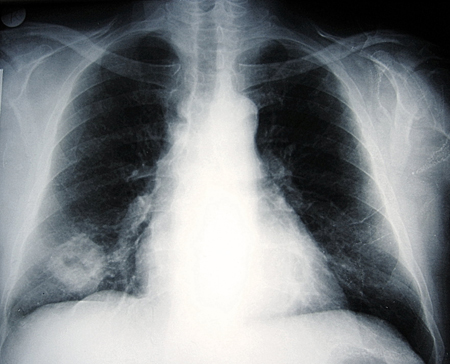

[Figure caption and citation for the preceding image starts]: Chest x-ray showing a lung tumour with central cavitationFrom the collection of Dr Ioannis P. Kioumis [Citation ends].